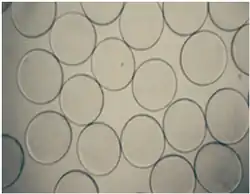

Microphotographs of the alginate-chitosan (AC) microcapsules.

Microphotographs of the alginate-chitosan (AC) microcapsules